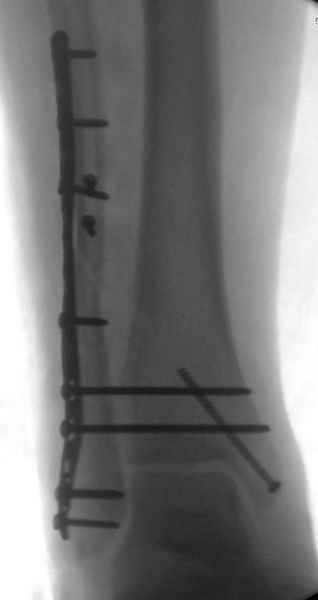

Мы бы, сблизив берцовые кости чрескожно наложенным репозиционным зажимом, провели позиционный межберцовый винт чуть ниже пластинки в положениий максимального тального сгибания стопы и ... на следующий день разрешили бы полностью наступать без гипса, брейса и т.п., но в обуви с небольшим каблуком 2-3 см и супинатором. Через месяц-полтора -винт удалить (если конечно не сломается).

Выполнено действительно неплохо, только позиционный винт забыли провести.

Вот и я тоже так думаю.

Присоединяюсь к ранее высказанным мнениям о необходимости вмешательства.

Перелом типа Вебер С с эверсионным механизмом травмы всегда сопровождается повреждением дистального межберцового синдезмоза, поэтому вместе с фиксацией переломов лодыжек( малоберцовой кости) автоматом выполняется фиксация синдесмоза винтом, который обычно удаляется через 8 недель -

перед началом полной нагрузки на ногу.

Спустя 4 недели закрытая ( без отрытия зоны синдесмоза) репозиция может оказаться проблематичной, но все равно стоит попробовать из 1см разреза ввести тягловый винт и нтраоперационно проконтролировать межберц. синдесмоз. Предварительно стоит обсудить с больным вероятность открытия синдесмоза при безуспешности закрытой репозиции.

С мнением «провести позиционный межберцовый винт чуть ниже пластинки в положениий тыльного сгибания стопы» согласен, но я бы нагрузку начал через три недели и удаление шурупа можно провести через 6-8 недель.

Для облегчения удаления сломанных шурупов (случается часто) рекомендую фиксацию двумя 3.5мм кортикальными шурупами на 3 мм длиннее, тот же сломанный шуруп легко удаляется с медиальной стороны.

Здесь похожий случай трехнедельной давности, перелом почти сросся и была укорочена малоберцовая, на операции длину малоберцовой смогли восстановить только после того, когда проксимальнее пластины ввели шуруп и использовали его как толкатель, с помощбю дистракционого инструмента (lamina spreader).

Меньше всего волнует положение медиальной лодыжки - в любое время можно провести остео или реостеосинтез, при несращении можно просто резецировать без ущерба для движений в голеностопе. Здесь обошлись фиксацией одним 4 мм канюлированным шурупом.